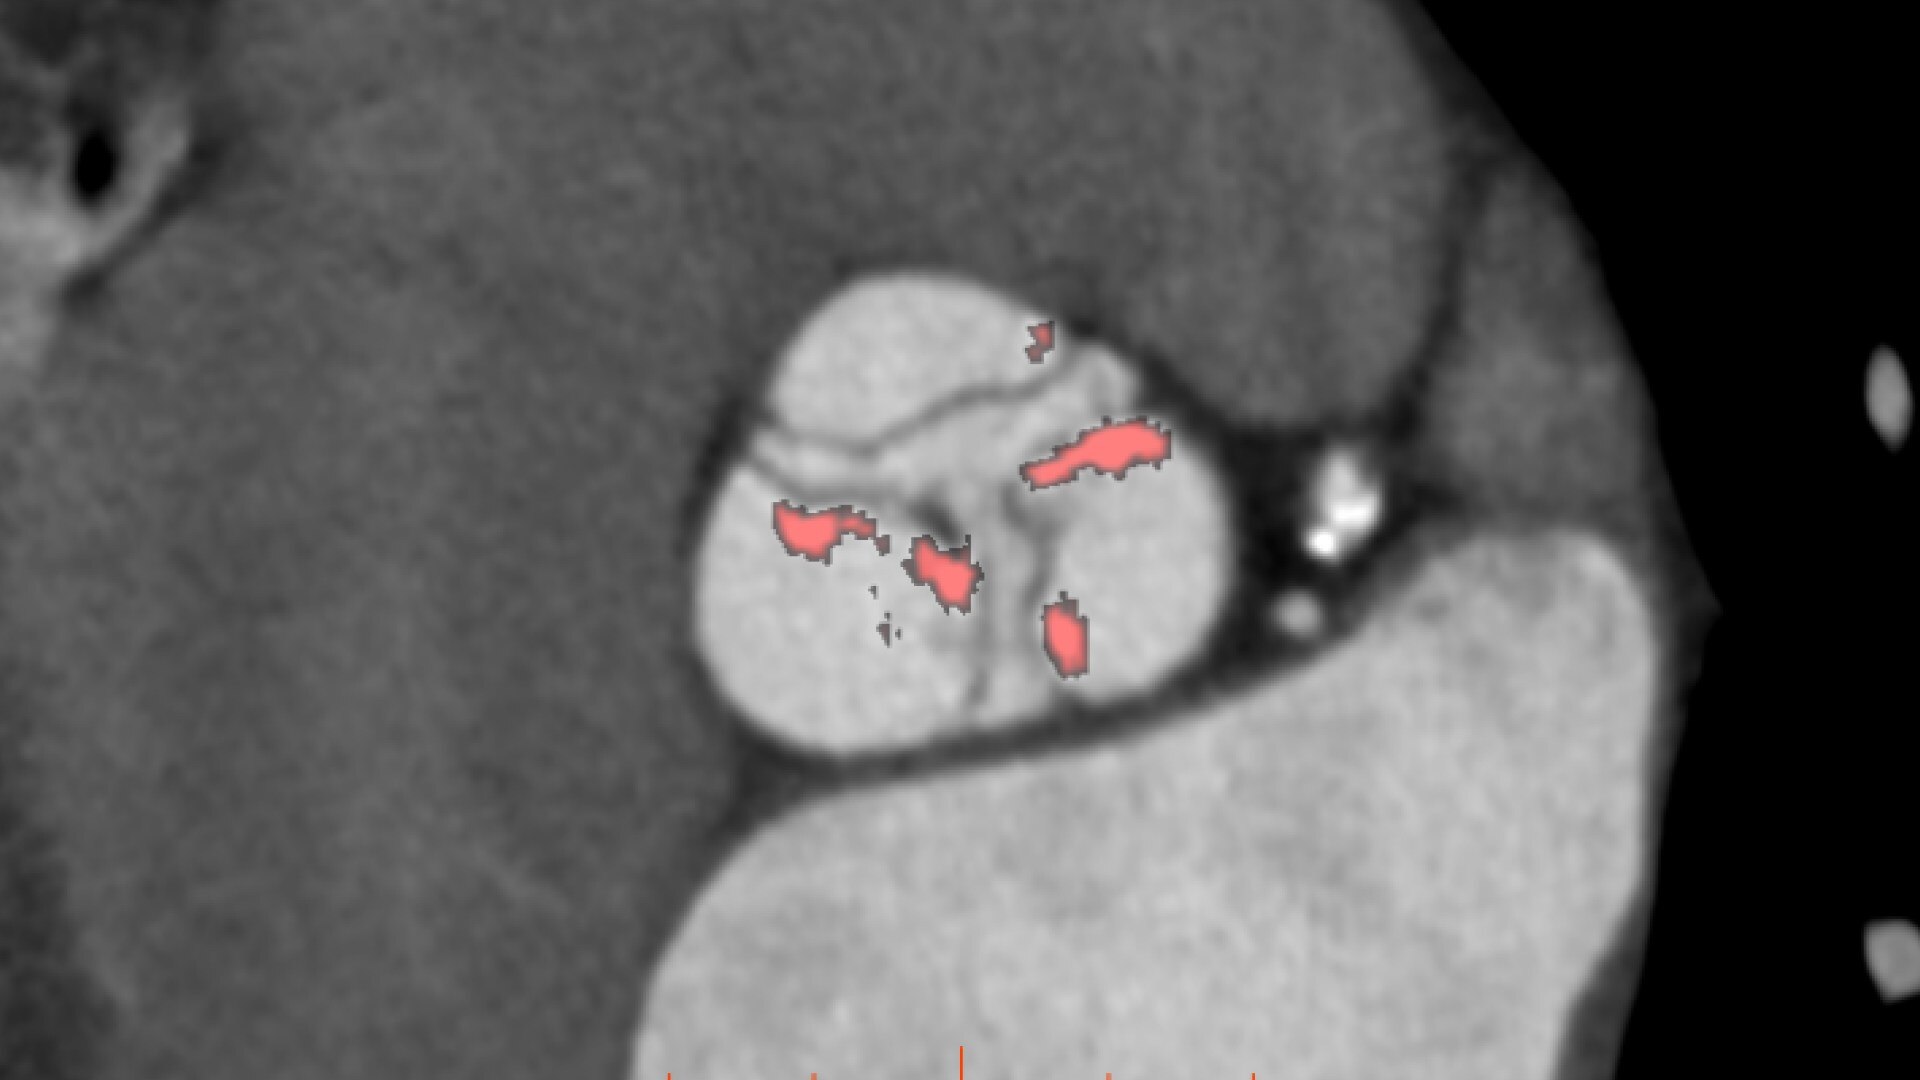

• Automatic estimate of aortic valve calcium volume measurement